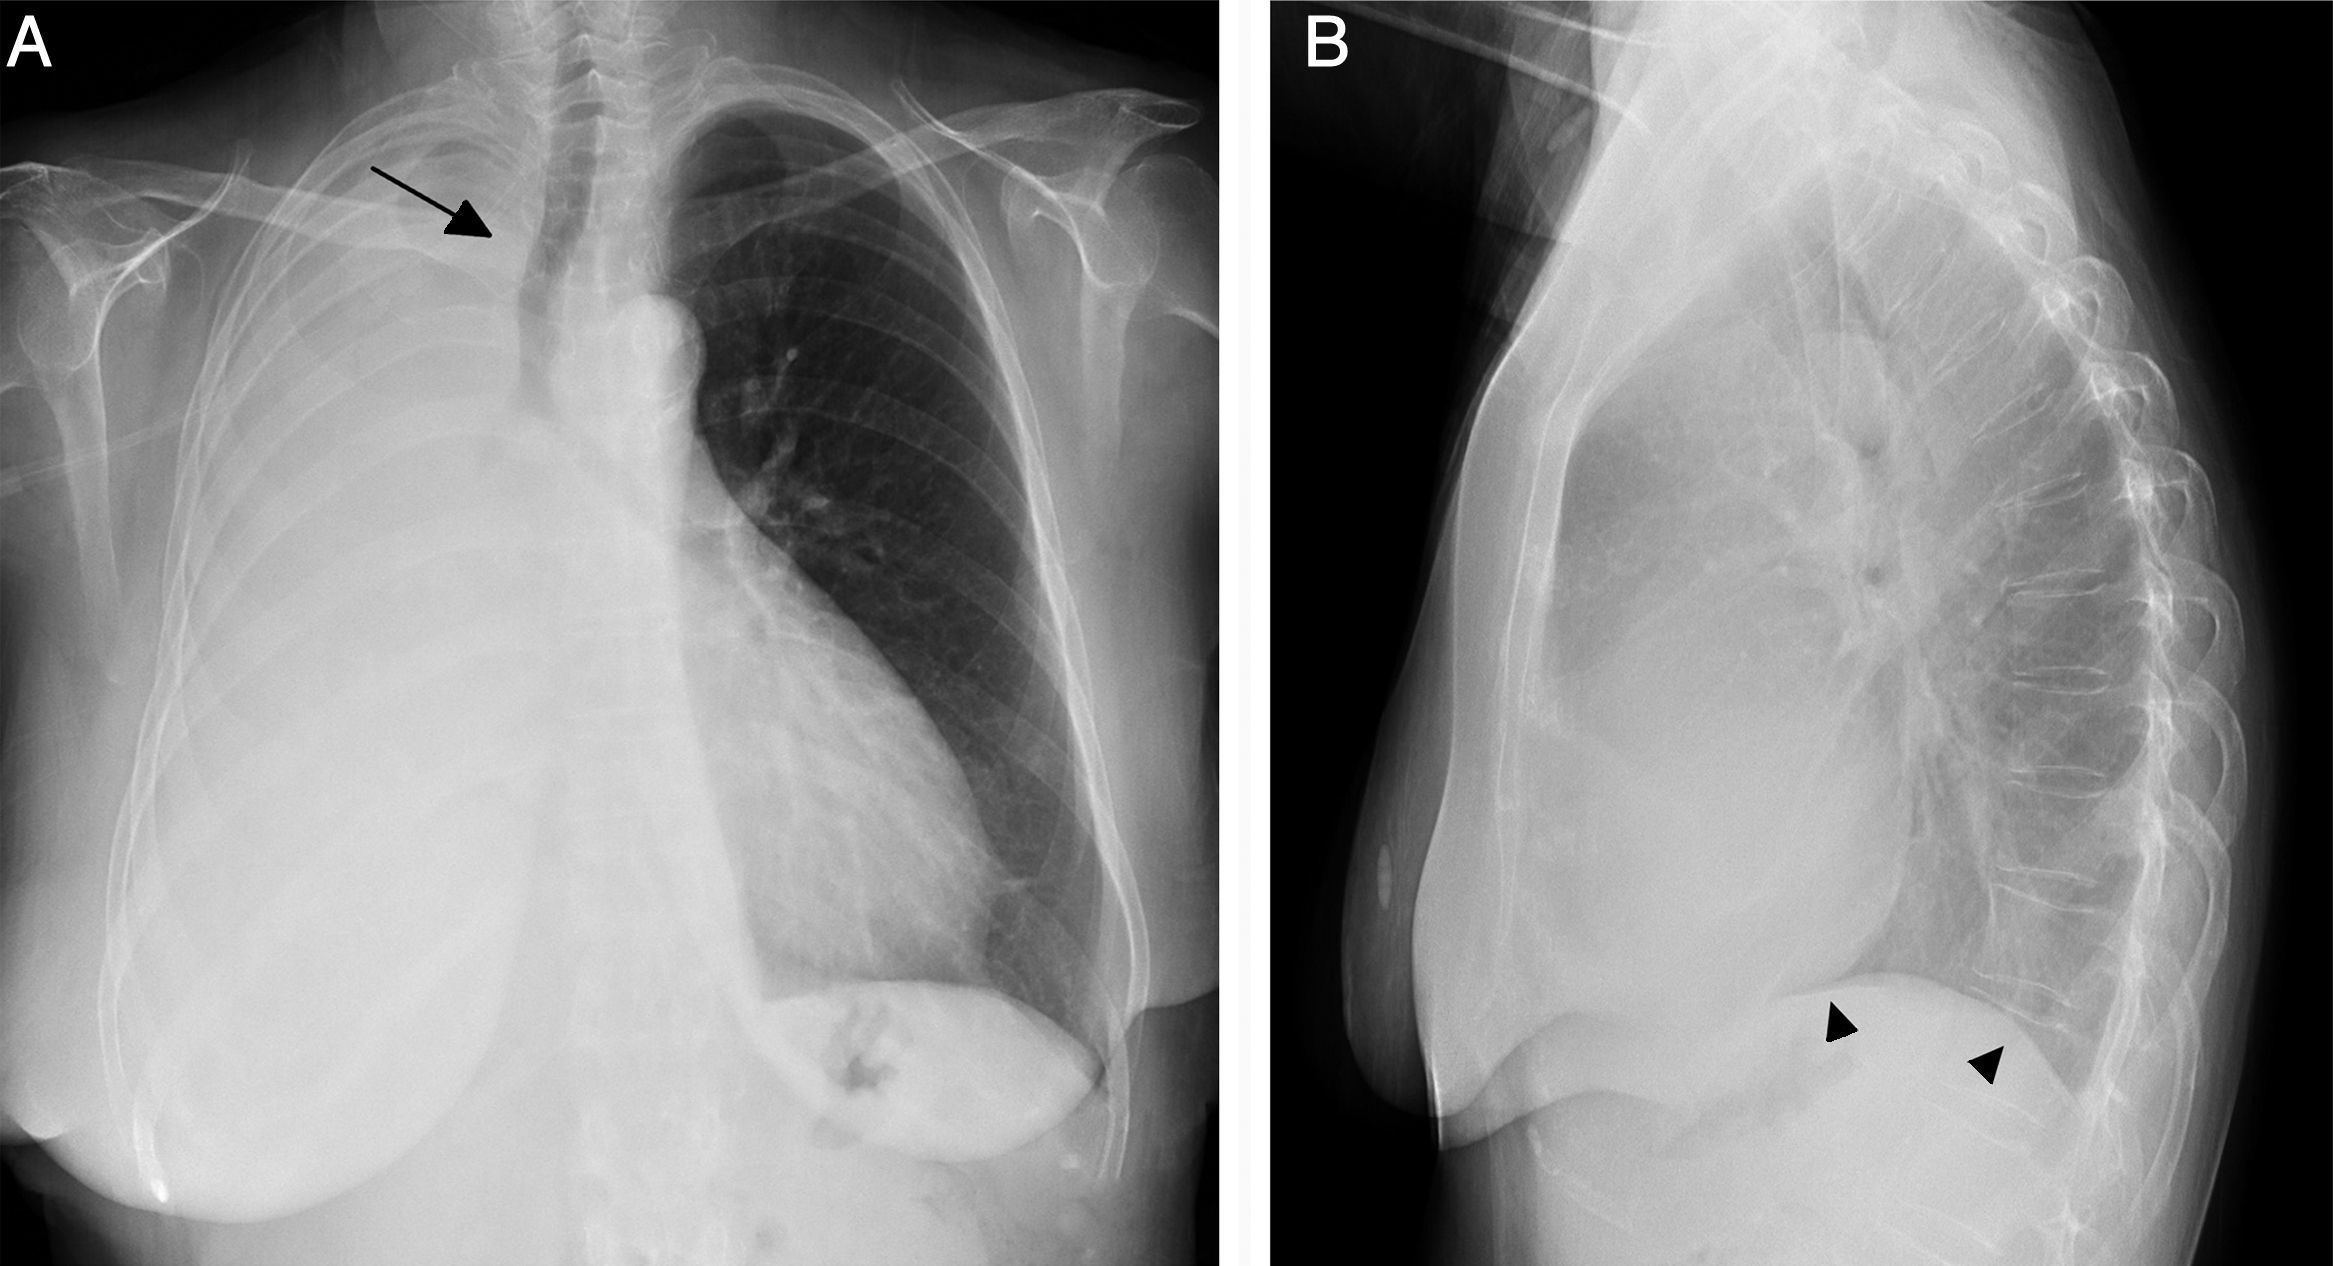

Atelectasis is an important indicator of potentially severe underlying disease that must be diagnosed as early as possible. One of the most common mechanisms is the reabsorption of air distal to respiratory tract obstruction. The chest X-ray is an excellent tool to diagnose atelectasis, and it is especially useful for ruling out central bronchial obstructions (e.g., from endobronchial tumors). If the signs of volume loss are not recognized correctly, the diagnosis and treatment can be delayed. This article describes the main findings of lobar atelectasis on chest X-rays and their correlations with CT findings, including the classic signs described in the literature and other, less known and sometimes subtle signs.